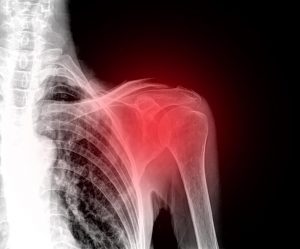

肩の痛みを解消する自然療法

肩の関節には、痛み、腫れ、可動域の制限などを引き起こす様々な怪我がありますが、怪我をしても医師による治療を受けない時には、慢性的な炎症や痛みを引き起こすことがあります。

病理学および肩の痛みの最も一般的な原因

肩の痛みに関連する最も一般的な疾患は次のとおりです:

- 変形性関節症

- 関節炎

- 腱炎

- 石灰性腱炎